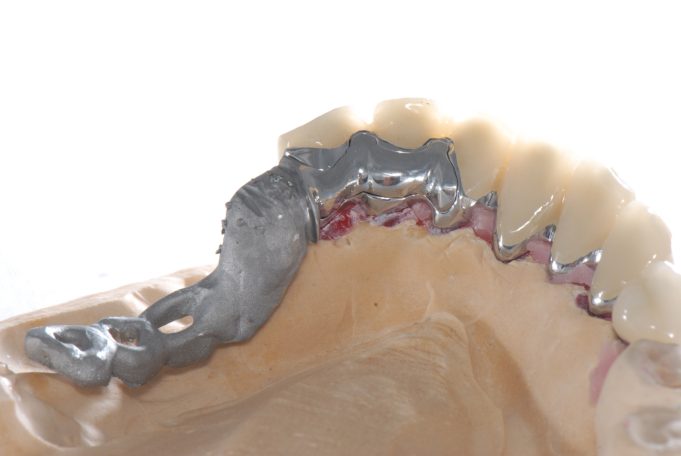

Implantsteg verankerte Brücke. Für den Patienten abnehmbar, aber der Tragekomfort von festen Zähnen.